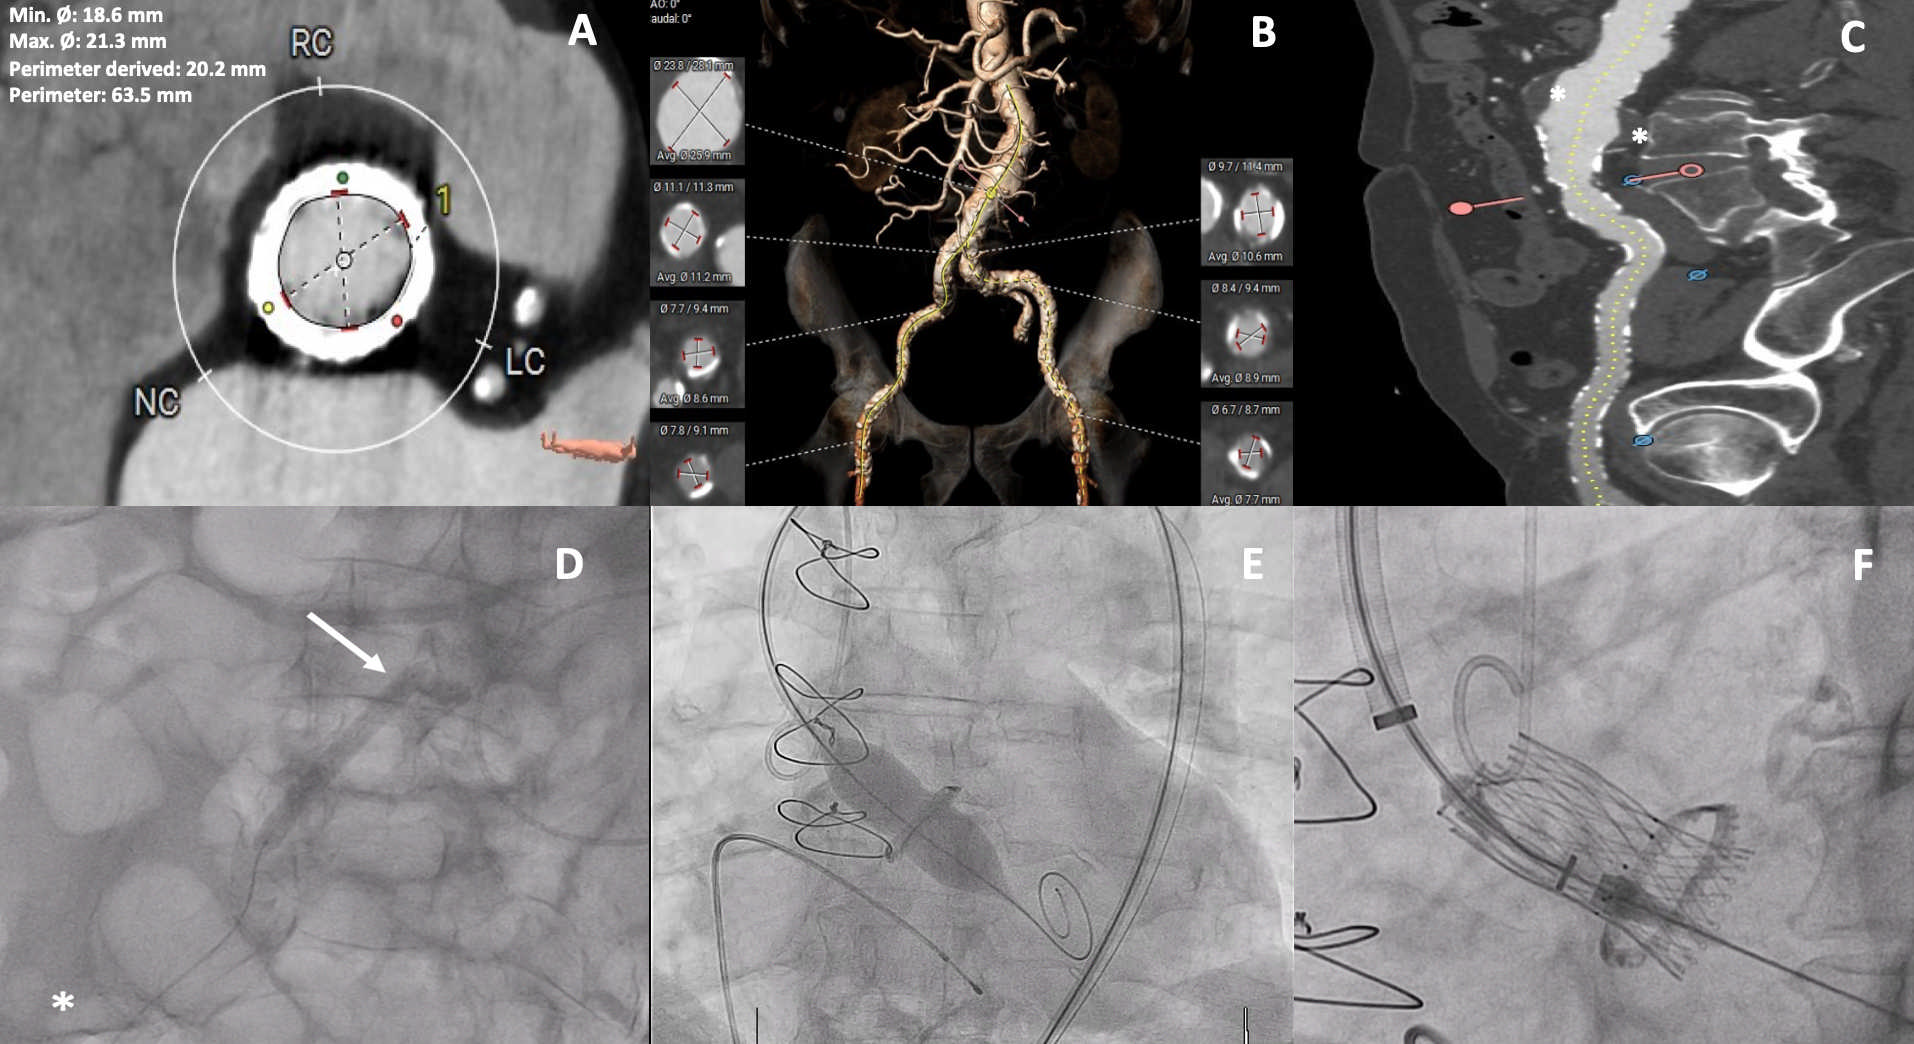

An 87-year-old man with a history of heart failure and a modified bio-Bentall Mitroflow 23-mm bioprosthesis (Sorin) was referred to our institution for critical aortic stenosis, which was confirmed by transesophageal echocardiography. Pre-procedural computed tomography revealed slightly calcified bioprosthesis leaflets, adequate coronary ostia height, and a slightly angled Bentall tube graft measuring 29 mm in diameter at the aortic anastomosis (Figure A).

Considering the high surgical risk (EuroScore II 17.8%), a valve-in-valve procedure was deemed necessary. The femoral access was compromised by extensive calcification and an infrarenal aneurysm with a thrombus extending into both femoral arteries (Figure B and C). To address this, intravascular lithotripsy was performed using a Shockwave medical device, which delivered 5 cycles of 30 pulses via a 7- x 60-mm balloon to the right common femoral artery (Figure D, Video 1). A 20- x 40-mm Atlas Gold balloon (BD) was then advanced through the right femoral artery sheath to crack the Mitroflow aortic bioprosthesis (Figure E). Subsequently, a 23-mm ALLEGRA transcatheter valve (Biosensors) was implanted into the degenerated bioprosthesis, resulting in a mean valve gradient reduction to 3 mm Hg with no significant insufficiency (Figure F, Video 2). No intraoperative complications occurred. The delivery system was removed, and femoral access was closed using a MANTA 18-French vascular closure device (Teleflex) (Video 3). The patient was discharged without complications.

This image underscores the pivotal role of advanced imaging in facilitating valve-in-valve interventions for high-risk patients with restricted access, showcasing the precise procedural execution and highlighting minimal postoperative recovery.